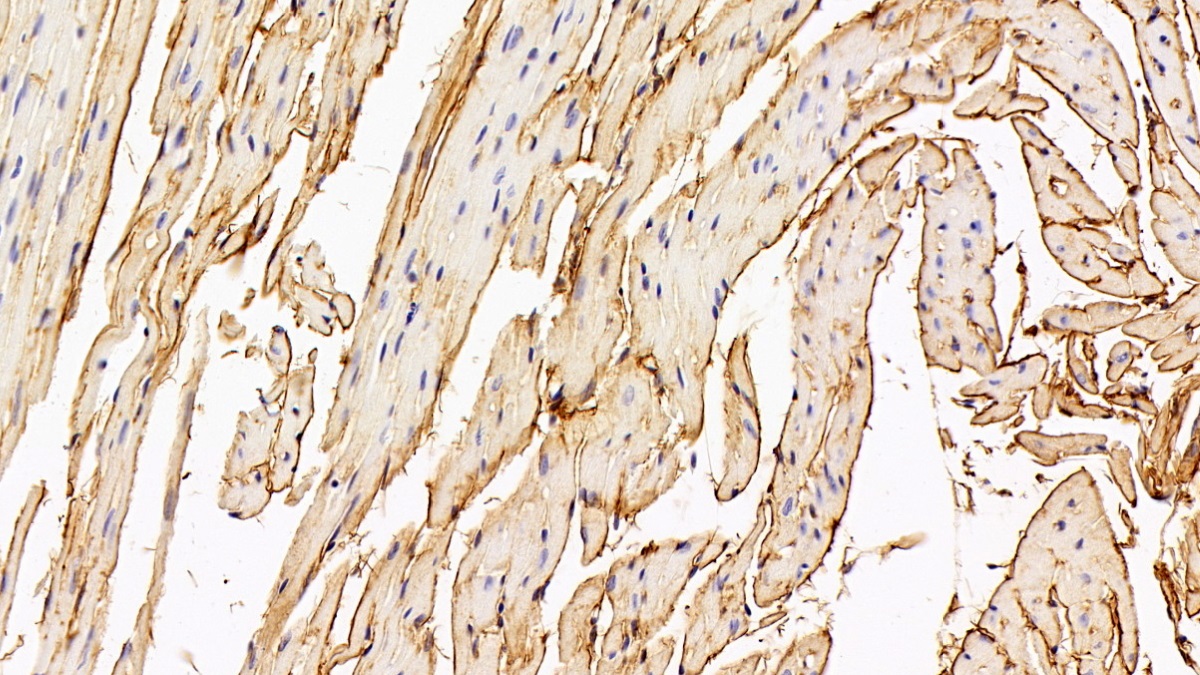

Использование высококачественных первичных антител является неотъемлемым условием получения точных и воспроизводимых результатов в современных научных исследованиях. Например, в рамках онкологического исследования удалось достоверно идентифицировать экспрессию белка PD-L1, что сыграло ключевую роль в оценке потенциальной эффективности иммунотерапии. Применение надежных антител обеспечило стабильность сигнала и высокую специфичность детекции, что позволило получить данные, пригодные для публикации в рецензируемых научных изданиях.

Способы применения первичных антител

Первичные антитела используют в разных методах: от вестерн-блоттинга до иммунофлюоресценции и проточной цитометрии. Всё решает подготовка: нужно грамотно выбрать буфер, точно рассчитать, сколько продукта добавить, и не затянуть с инкубацией. Например, в вестерн-блоттинге без правильной блокировки мембраны фон может всё испортить, а в иммунофлюоресценции фиксация клеток решает, будет ли сигнал ярким. Мы не просто продаём реагенты, а помогаем довести эксперимент до результата: подбираем реагенты и даём советы по методам, если есть специфика в протоколах производителя. Нужен особый подход? Оформите спецзаказ по ссылке — мы найдём решение для вашего проекта.